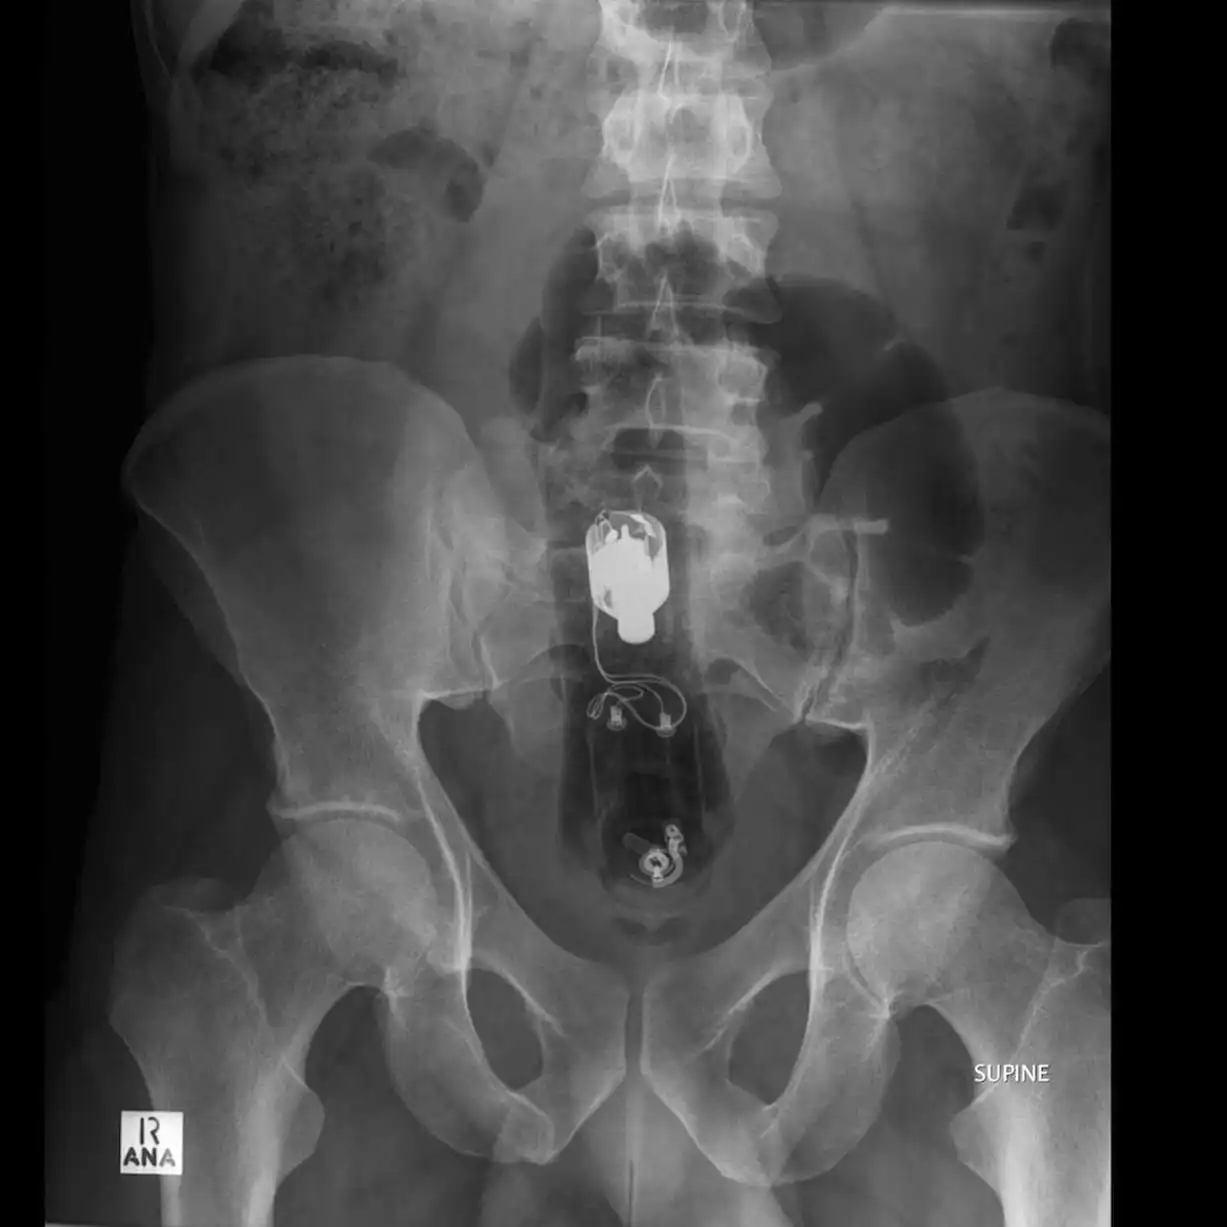

Врачебные находки в интимных местах

Или как впихнуть невпихуемое :lol: